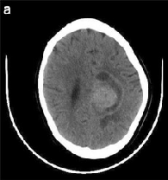

脑胶质瘤

胶质瘤存活率是多久?

胶质瘤存活率是多久?有不同类型的神经胶质瘤,即星形细胞瘤,少突胶质细胞瘤,胶质母细胞瘤(GBM)和弥散性神经胶质瘤。此外,低KPS是神经胶质瘤患者治疗后一年和长期存活中...